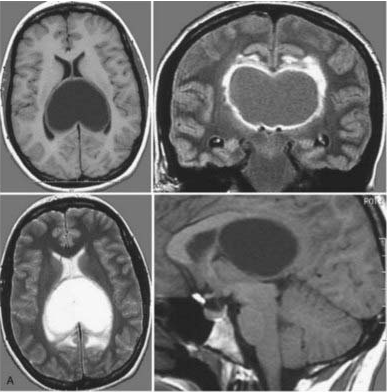

.1. 与瘤共存6年 希望越大,失望越大 10岁,林林被查出一个位于松果体区的钙化病变。由于位置特殊,体积较小,医生均建议保守观察。钙化,意味着肿瘤生长缓慢,林林一家放下心来,希望在...